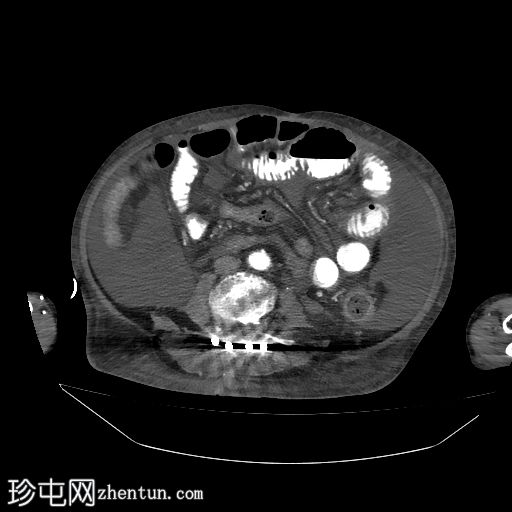

轴位增强扫描(门静脉期)

显示结肠壁环周增厚,尤其横结肠增厚,充血强化的黏膜覆盖于增厚的黏膜下皱襞之上,伴有结肠周围脂肪条索影和大量腹腔内游离液体。

少量右侧胸腔积液。

小肠袢未见异常。

该老年男性患者,两个月前曾接受脊柱手术,并多次服用抗生素,现因急性腹痛和腹胀就诊。CT检查结果提示结肠炎,在此临床情况下最可能是假膜性结肠炎。